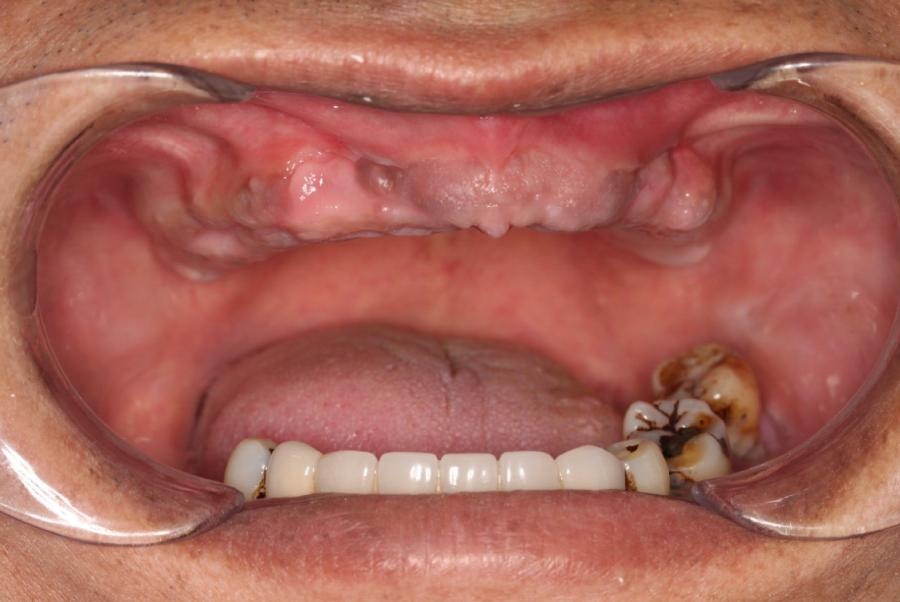

Tình trạng răng của anh Long MLee trước khi trồng Implant.

Khi sử dụng hàm tháo lắp, anh Long MLee lại gặp phải nhiều trở ngại trong ăn uống. Anh không còn thưởng thức được những món ăn yêu thích của mình bởi hàm tháo lắp vốn chỉ đáp ứng được 30% khả năng ăn nhai. Không những vậy, vì để trống răng quá lâu nên phần má của anh bị hóp vào, giọng nói cũng thay đổi.